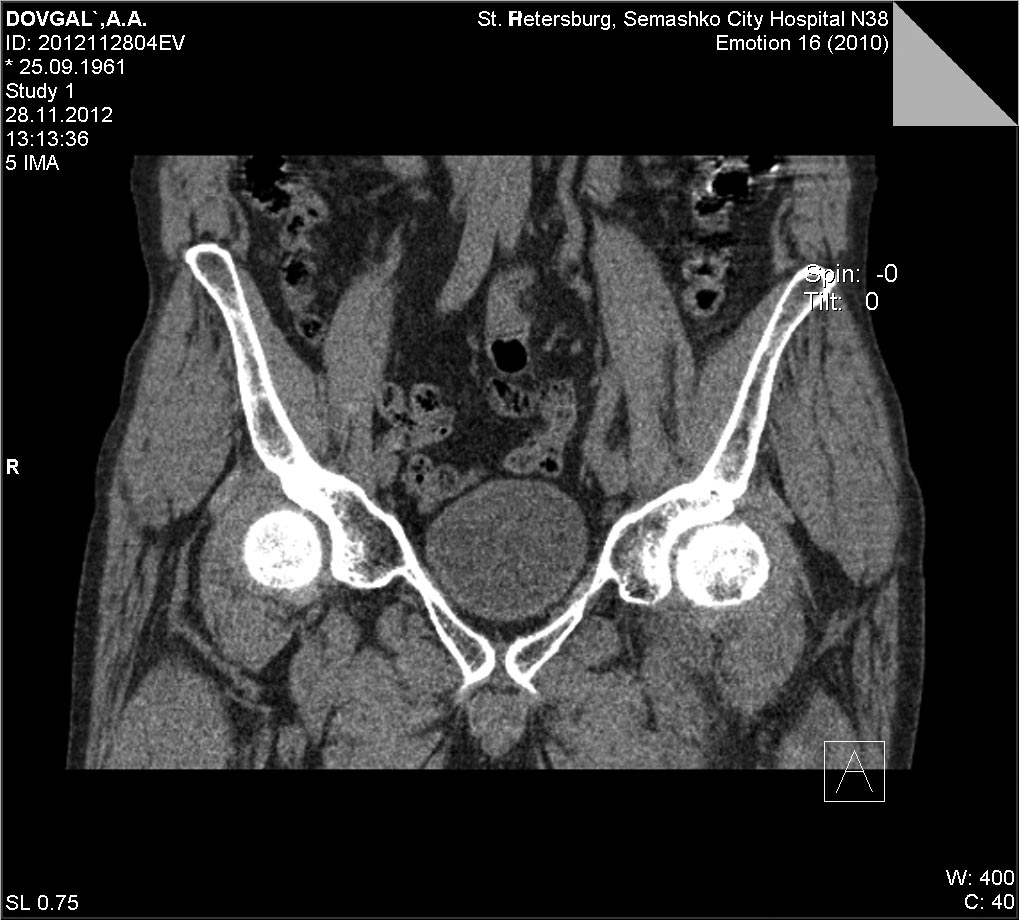

[Ortho] Импрессионный перелом головки бедренной кости

КТ

Вложение не в текстовом формате было извлечено…

Имя     : 05FD4209.jpg

Тип     : image/jpg

Размер  : 149254 байтов